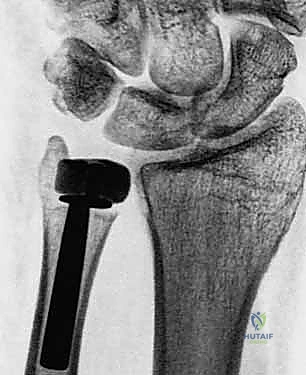

2. التصوير بالأشعة السينية (X-rays)

تُعد الأشعة السينية الخطوة الأولى والأساسية. توضح التآكل الغضروفي، وتكّون النتوءات العظمية، والتغيرات في محاذاة العظام. يقوم الدكتور هطيف بطلب صور في وضعيات محددة (أثناء الكب والاستلقاء) لتقييم الديناميكية الحركية.

3. إزالة العظم التالف وتحضير القناة

يتم فتح كبسولة المفصل. إذا كان رأس الزند موجودًا ولكنه مشوه، يتم قصه باستخدام منشار جراحي دقيق. في الحالات التي تم فيها استئصال رأس الزند مسبقًا، يتم تنظيف جذع الزند المتبقي. بعد ذلك، يتم تحضير القناة النخاعية داخل عظم الزند باستخدام مباسط (Broaches) متدرجة الحجم لاستقبال جذع المفصل الصناعي.

4. اختيار وتجربة المفصل الصناعي (Sizing and Trialing)

هذه خطوة حاسمة. يقوم الدكتور هطيف بوضع نماذج تجريبية (Trials) للمفصل الصناعي بأحجام مختلفة. يتم اختبار حركة الساعد (الكب والاستلقاء) للتأكد من السلاسة، والاستقرار، وعدم وجود أي احتكاك، والتأكد من استعادة الطول الصحيح للزند.